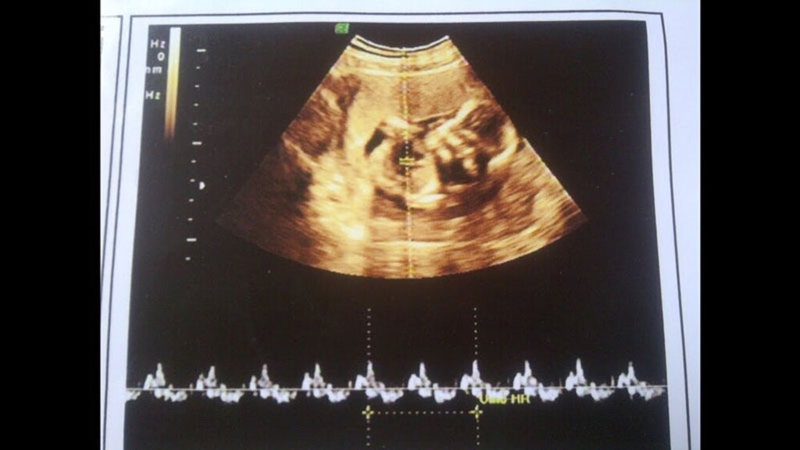

Câu hỏi được các mẹ thường xuyên đặt ra chính là thời gian siêu âm tim thai ở tuần thứ mấy? Thời gian phổ biến để thực hiện siêu âm tim thai là vào tuần thứ 7 hoặc tuần thứ 8 của thai kỳ. Tuy nhiên, tim thai thường hình thành từ tuần thứ 5, và cũng có trường hợp tim thai xuất hiện muộn hơn vào khoảng tuần thứ 9. Siêu âm tim thai tuần thứ 8 thường đem lại kết quả khá chính xác và đó cũng là thời điểm mà các bác sĩ thường yêu cầu thai phụ thực hiện thăm khám.

Thời điểm thích hợp để siêu âm thai lần đầu là từ tuần thứ 6 đến tuần thứ 8 của thai kỳ. Tuy nhiên, có những trường hợp đặc biệt khi tim thai mới xuất hiện vào tuần thứ 10. Do đó, nếu siêu âm lúc 6 tuần chưa thấy tim thai, mẹ không cần lo lắng. Trong giai đoạn các tuần đầu mang thai các mẹ nên thường xuyên nghe theo chỉ định của bác sĩ để lắng nghe nhịp tim đập của các con yêu.

Thông thường tim thai sẽ bắt đầu hình thành từ tuần thứ 5 trong thai kỳ. Nhưng còn tùy thuộc nhiều yếu tố, có một số trường hợp tim thai thường xuất hiện muộn hơn vào khoảng thời gian ở tuần thứ 9. Rất khó để biết được khoảng thời gian thích hợp để tiến hành siêu âm tim thai cho ra kết quả khá chính xác. Chính vì thế các mẹ hãy giữ tinh thần thoải mái trước khi tiến hành siêu âm tim thai.